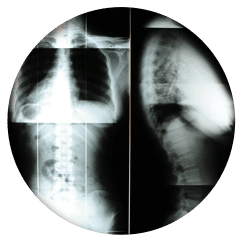

The Gonstead Technique relies on five essential components: Visualization, Instrumentation, Palpation, X-Ray, and patient symptoms. By integrating these elements, we can pinpoint the precise location that requires adjustment. When all these factors align, we can provide the patient with a specific and effective adjustment. Specificity is the key, as Dr. Gonstead emphasized that three adjustments on the wrong vertebral segment could lead to a Subluxation, highlighting the importance of precision.

Dr. Gonstead's Level Disc Theory asserts that "anatomically and physiologically normal discs promote optimum vertebral alignment." This is evidenced when the vertical height of a vertebral couple is uniform around 360 degrees, with the vertebral bodies properly aligned. This alignment, known as "Parallel Discs," ensures even weight distribution, adequate nutrient flow, and optimal joint function and movement within the spine.